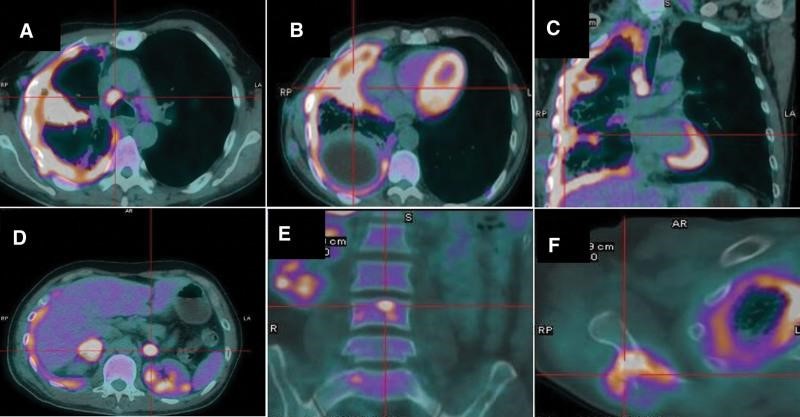

患者男性,54 岁,每年吸烟约 30包,咳嗽、胸痛 1 个月,2019 年 11 月入我院,胸部 CT 示有 2 cm 肿块,有空洞。右肺中叶,纵隔淋巴结肿大,右胸膜弥漫性胸膜增厚,右胸胸腔积液。随后的正电子发射断层扫描-计算机断层扫描 (PET-CT) 扫描证实了右肺肿块和厚胸膜中葡萄糖代谢异常增加(图 1A-C)。它还显示双侧肾上腺、右侧肩胛骨和多个椎骨的全身转移(图 1D-F)。实验室检查结果在正常范围内,除了碳水化合物抗原 125 水平升高, 为490.2 U/ml 。进行了胸腔穿刺术,但在反复剥脱细胞学检查后,引流的胸腔液中未发现肿瘤细胞。接下来,支气管镜检查显示右中支气管开口处有压缩性支气管狭窄,但病理结果显示没有恶性细胞。随后对肿块进行CT引导下细针穿刺活检,活检标本病理仅显示凝固性坏死和肺组织异常。贼后,使用电视胸腔镜进行胸膜活检,活检标本呈恶性肿瘤细胞。免疫组化染色显示肿瘤TTF-1和Napsin A阴性,但P40和CK5/6阳性(图 2A-C)。因此,该患者被诊断为鳞状细胞肺癌(美国癌症联合委员会第 8 版 T3N2M1c,IVB 期)。通过 ARMS-PCR 程序检测 EGFR 外显子 19 缺失突变。使用抗体 22C3 (Dako pharmDx) 对 PD-L1 表达的评估显示 肿瘤阳性细胞数 为 90%(图2D)。

图1:PET-CT扫描。PET-CT显示右肺肿块糖代谢异常增加,纵隔淋巴结肿大,右侧胸膜弥漫性增厚。此外,还发现了双侧肾上腺、右侧肩胛骨和多处椎骨的全身转移。